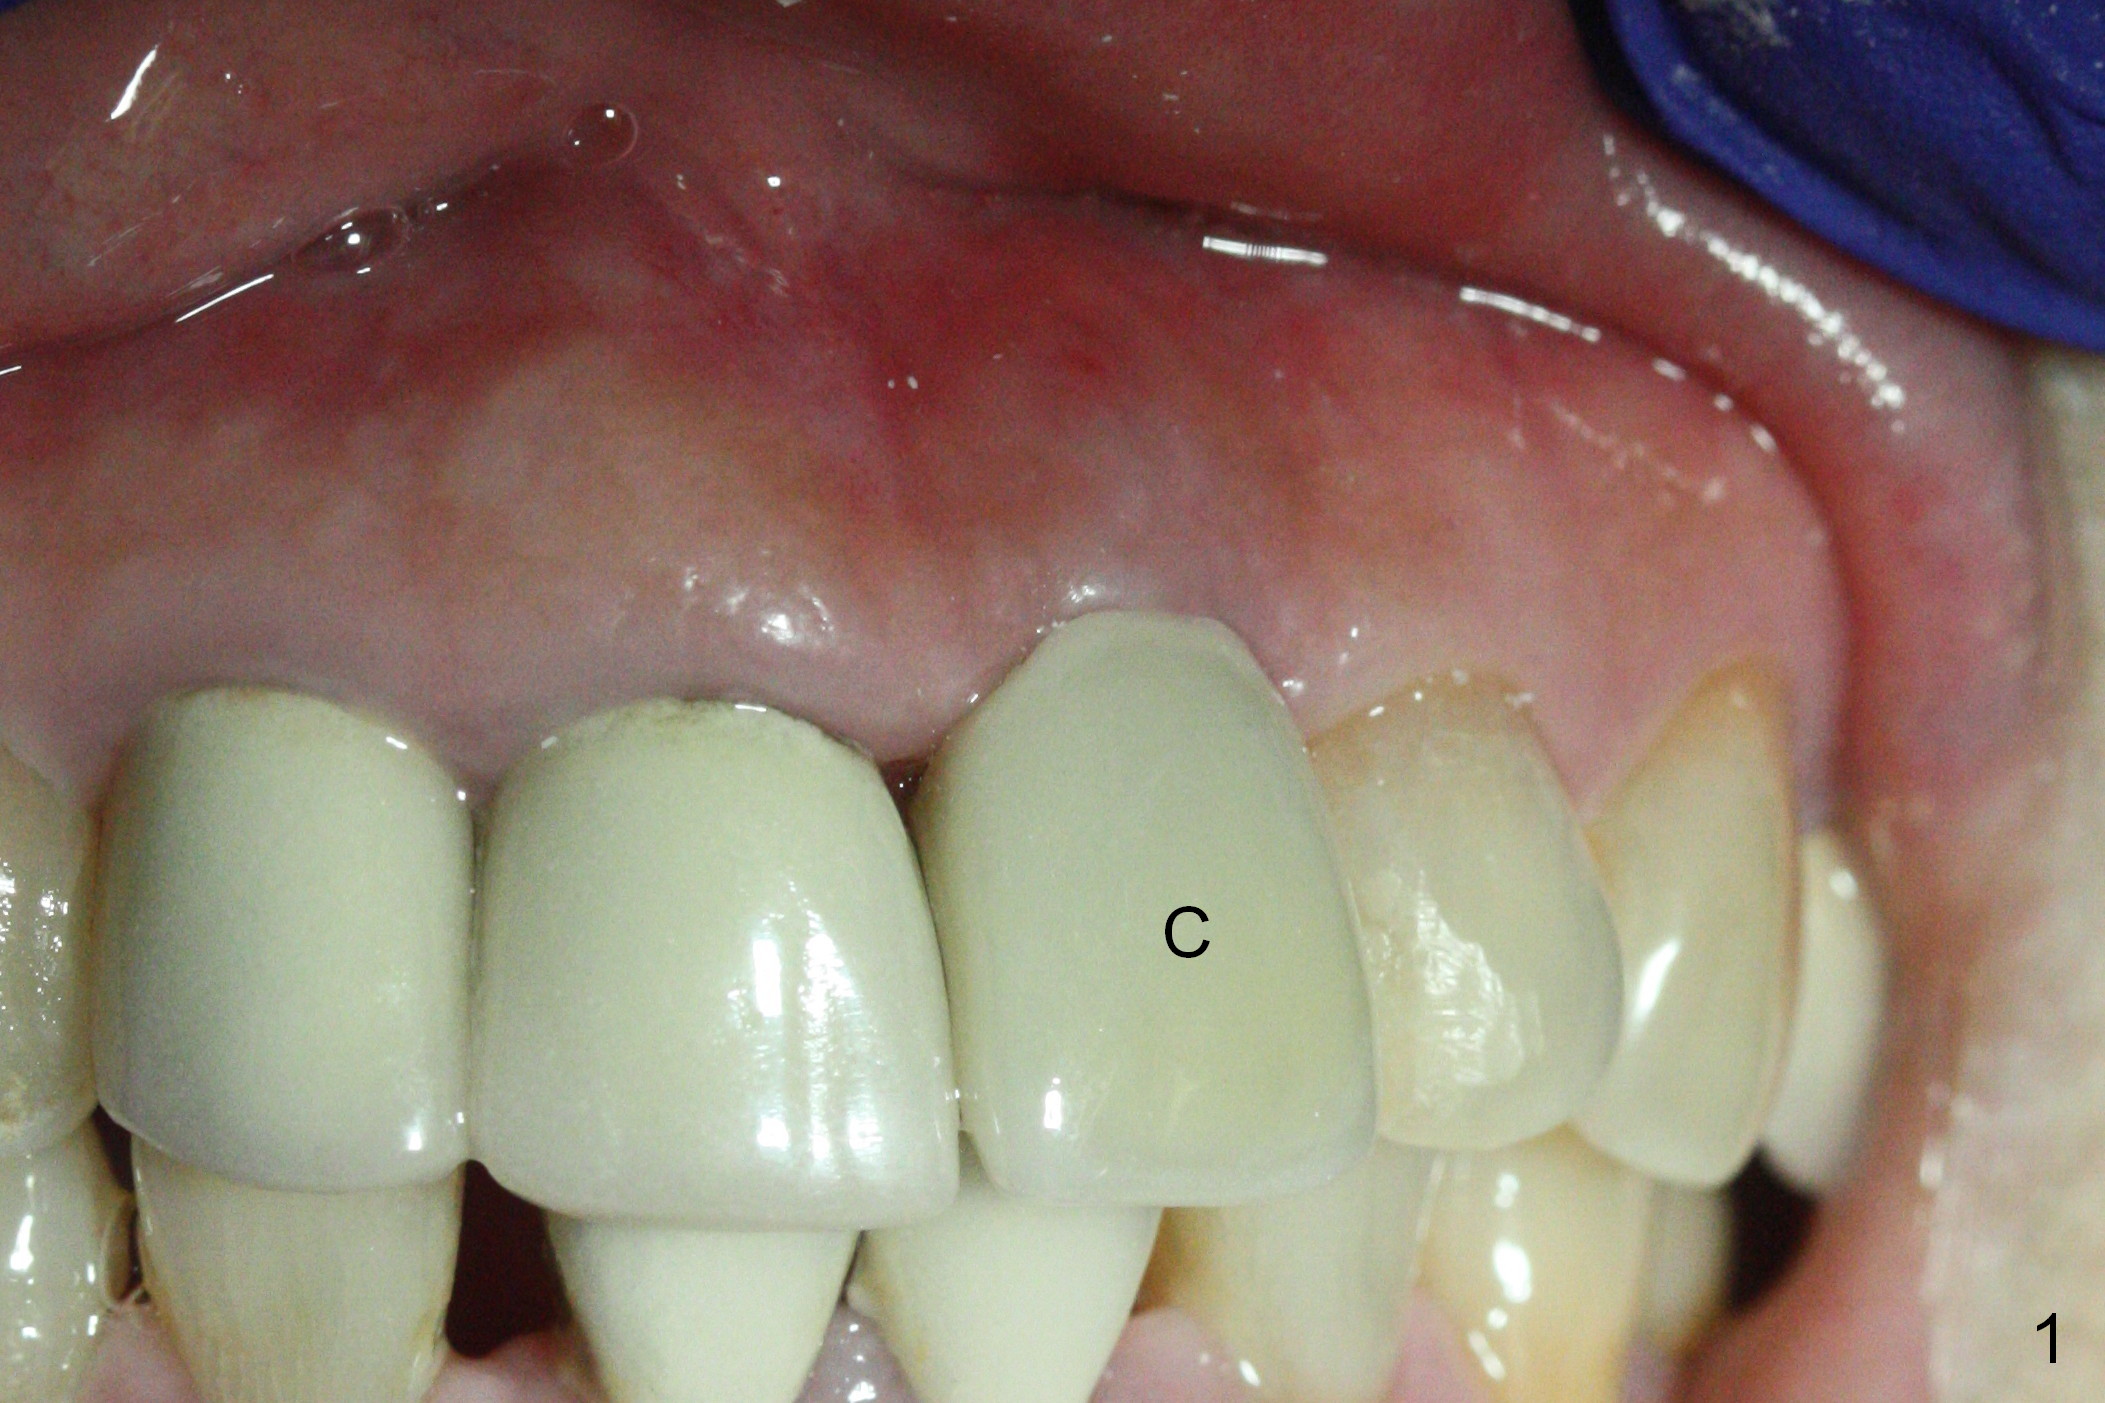

When a permanent crown (Fig.1 C) is seated 5 months postop, it looks too long and bulky (as well as metal show through cervically), which is in turn due to buccal placement of the crown (Fig.2) and abutment (Fig.3).  By mistake, abutment is changed from 4.5x15°, 3 mm cuff to 4.5x15°, 2 mm cuff (Fig.4-6); the profile appears to improve.  After prep (buccoincisal (Fig.4 ^) and linguoincisal), impression is taken.  The gold coating in the buccocervical area is untouched so that there should be no or minimal metal show through.  Please make a new crown as cosmetic as possible (not too bulky, especially buccocervical).  If you feel that the result will be the same as before, return the case.  The angled abutment may be changed 25°.  In fact the new crown looks better.